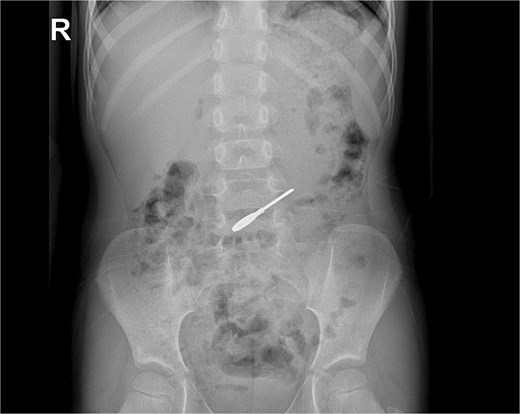

On clinical evaluation, a completely asymptomatic patient was encountered; she was extremely nervous. However, her vital signs were normal, and she had no abdominal pain or tenderness. She passed gas and had no issues with her bowel movements. Due to this, an abdominal X-ray was requested, unveiling a foreign body (small key) in her abdomen. The foreign body appeared to be in her stomach or transverse colon; nonetheless, it did not cause any signs of obstruction (Fig. 1a and b). With these findings, the patient was admitted for close monitoring due to the risk of obstruction. An endoscopy was requested. However, it was completely normal, and the key was nowhere to be found as it had already passed through the pylorus. Another abdominal X-ray was done 48 hours after admission, showing that the foreign body was moving along the intestines (Fig. 2).

(a) X-ray: A full key is seen ingested, no pneumoperitoneum or signs of obstruction. (b) X-ray: the key is seen in the intestine.